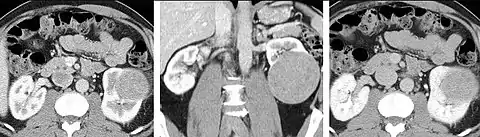

Detection and characterization of renal parenchymal masses is a frequent indication for CT. An initial noncontrast CT is important for detecting calcium or fat in a lesion, and to provide baseline attenuation of any renal masses. Following noncontrast scanning, intravenous contrast is injected and a corticomedullary phase is obtained at approximately 70 seconds (figure 7a, 7b). The corticomedullary phase is characterized by enhancement of the renal cortex as well as the renal vasculature. This phase is valuable in the evaluation of benign renal variants, lymphadenopathy and vasculature, however certain medullary renal masses may not be visible during this phase due to minimal enhancement of the medulla and collecting system. The parenchymal phase is obtained approximately 100–200 seconds after the injection of contrast material (figure 7c). Parenchymal phase imaging demonstrates continued enhancement of the cortex, enhancement of the medulla, and various levels of contrast material in the collecting system. The parenchymal phase is highly important for the detection and characterization of renal masses, parenchymal abnormalities, and the renal collecting system. This method of imaging does not evaluate for abnormalities of the collecting system.

FIGURE 7. Selected images from a renal mass specific protocol CT. Corticomedullary phase (axial 7a) demonstrates peripheral enhancement of the renal cortex with minimal opacification of the renal medulla. There is a large renal cell carcinoma in the left kidney (right in image) which can be differentiated from the normal renal parenchyma by the heterogeneous and differential enhancement. The renal artery and vein are opacified in this phase as well. The collecting system is not opacified (coronal reformat 7b). In the parenchymal phase, the renal cortex and the medulla are enhancing. The renal cell carcinoma in the left kidney is not as well defined when compared to the corticomedullary phase images, but is actually slightly more conspicuous. There is some contrast noted within the collecting system during this phase (7c).